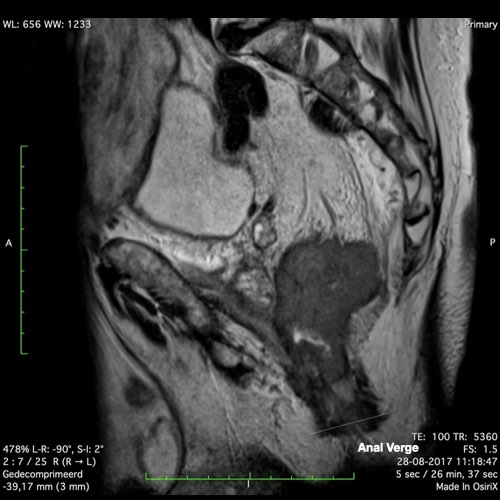

Hình ảnh

Các hình ảnh được cung cấp cho thấy ung thư biểu mô tế bào nhẫn với tình trạng dày lan tỏa thành trực tràng, hình ảnh bia bắn điển hình, và sự xâm lấn mỡ mạc treo trực tràng.